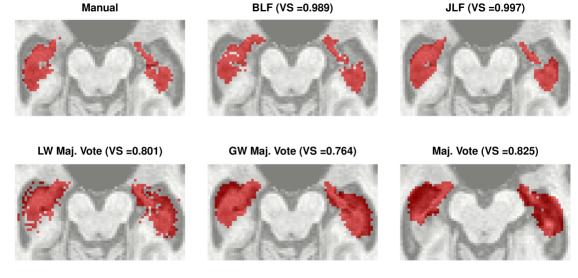

One can threshold the posterior probabilities to obtain a binary inclusion map. After thresholding, we compare the resulting segmentation to those obtained by simple majority voting, globally-weighted majority voting, locally-weighted majority voting, and JLF. The global weighting is inversely proportional to each atlas’ average intensity difference from the target. Local weighting is done similarly using voxel-specific intensity differences. Figure 9 displays one slice of the manual segmentation along with that which is obtained by thresholding the posterior inclusion probabilities at 0.5. The hippocampus is a relatively small structure compared to the full three-dimensional image (as can be seen in, e.g., Supplementary Figure 4). In this case, Taha and Hanbury (2015) argue that the Dice coefficient defined in Section 3 is not the best measure for evaluating a segmentation. However, the volume of the hippocampus is important for volumetry in the study of AD progression. Thus, we follow the suggestion of Taha and Hanbury (2015) and use the volume similarity as an evaluative metric, defined as , where and denote false negatives, false positives, and true positives, respectively. Bayesian label fusion attains . This is competitive with JLF, the current state-of-the-art (), and superior to both simple and weighted voting procedures. (VS values are displayed in Figure 9.)

As already mentioned, only healthy brains are used as atlases. The systematic differences are not completely captured by atlas-target image dissimilarities. Despite accounting for image dissimilarity, there is a tendency for the established methods to over-segment the hippocampus. The Bayesian label fusion model facilitates explicit incorporation of the estimated gray matter pattern as a predictor. Our prior specification allows for the possibility that the tissue classes are incorrectly assigned in some places, but are mostly reliable. The effect of the gray matter segmentation as auxiliary information can be clearly seen by comparing it even with our own model in which this information is ignored but the model is otherwise identical. Figure 10 displays the posterior inclusion probabilities obtained without using the gray matter information, along with the results already presented for reference. Using only the intensity-similarity-weighted distance labels yields a Bayesian regression analogue to the other approaches that only weight by intensity similarity. The additional tissue class information is able to prevent oversegmentation of the diseased structure.